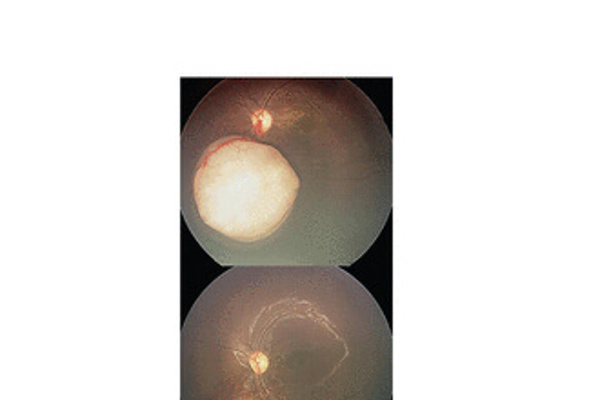

Cystoid macular oedema following cataract surgery